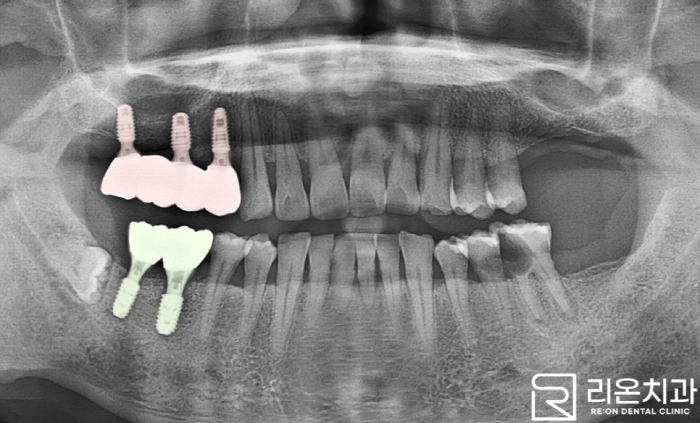

■ 4. 결과

주변 자연치들과 비교하여 심미성이 뛰어난 색을 활용해 보철 제작을 진행한 뒤 최종 종결되었습니다.

촬영일: 2023.11.17

리온 치과 에서는 아마도 치아의 심한 통증으로 오랜 시간 힘들어하셨을 거라 생각이 되는데요,

이제는 그런 걱정과 고민 없이 아름다운 미소와 즐거운 식사시간이 될 거라 생각됩니다.